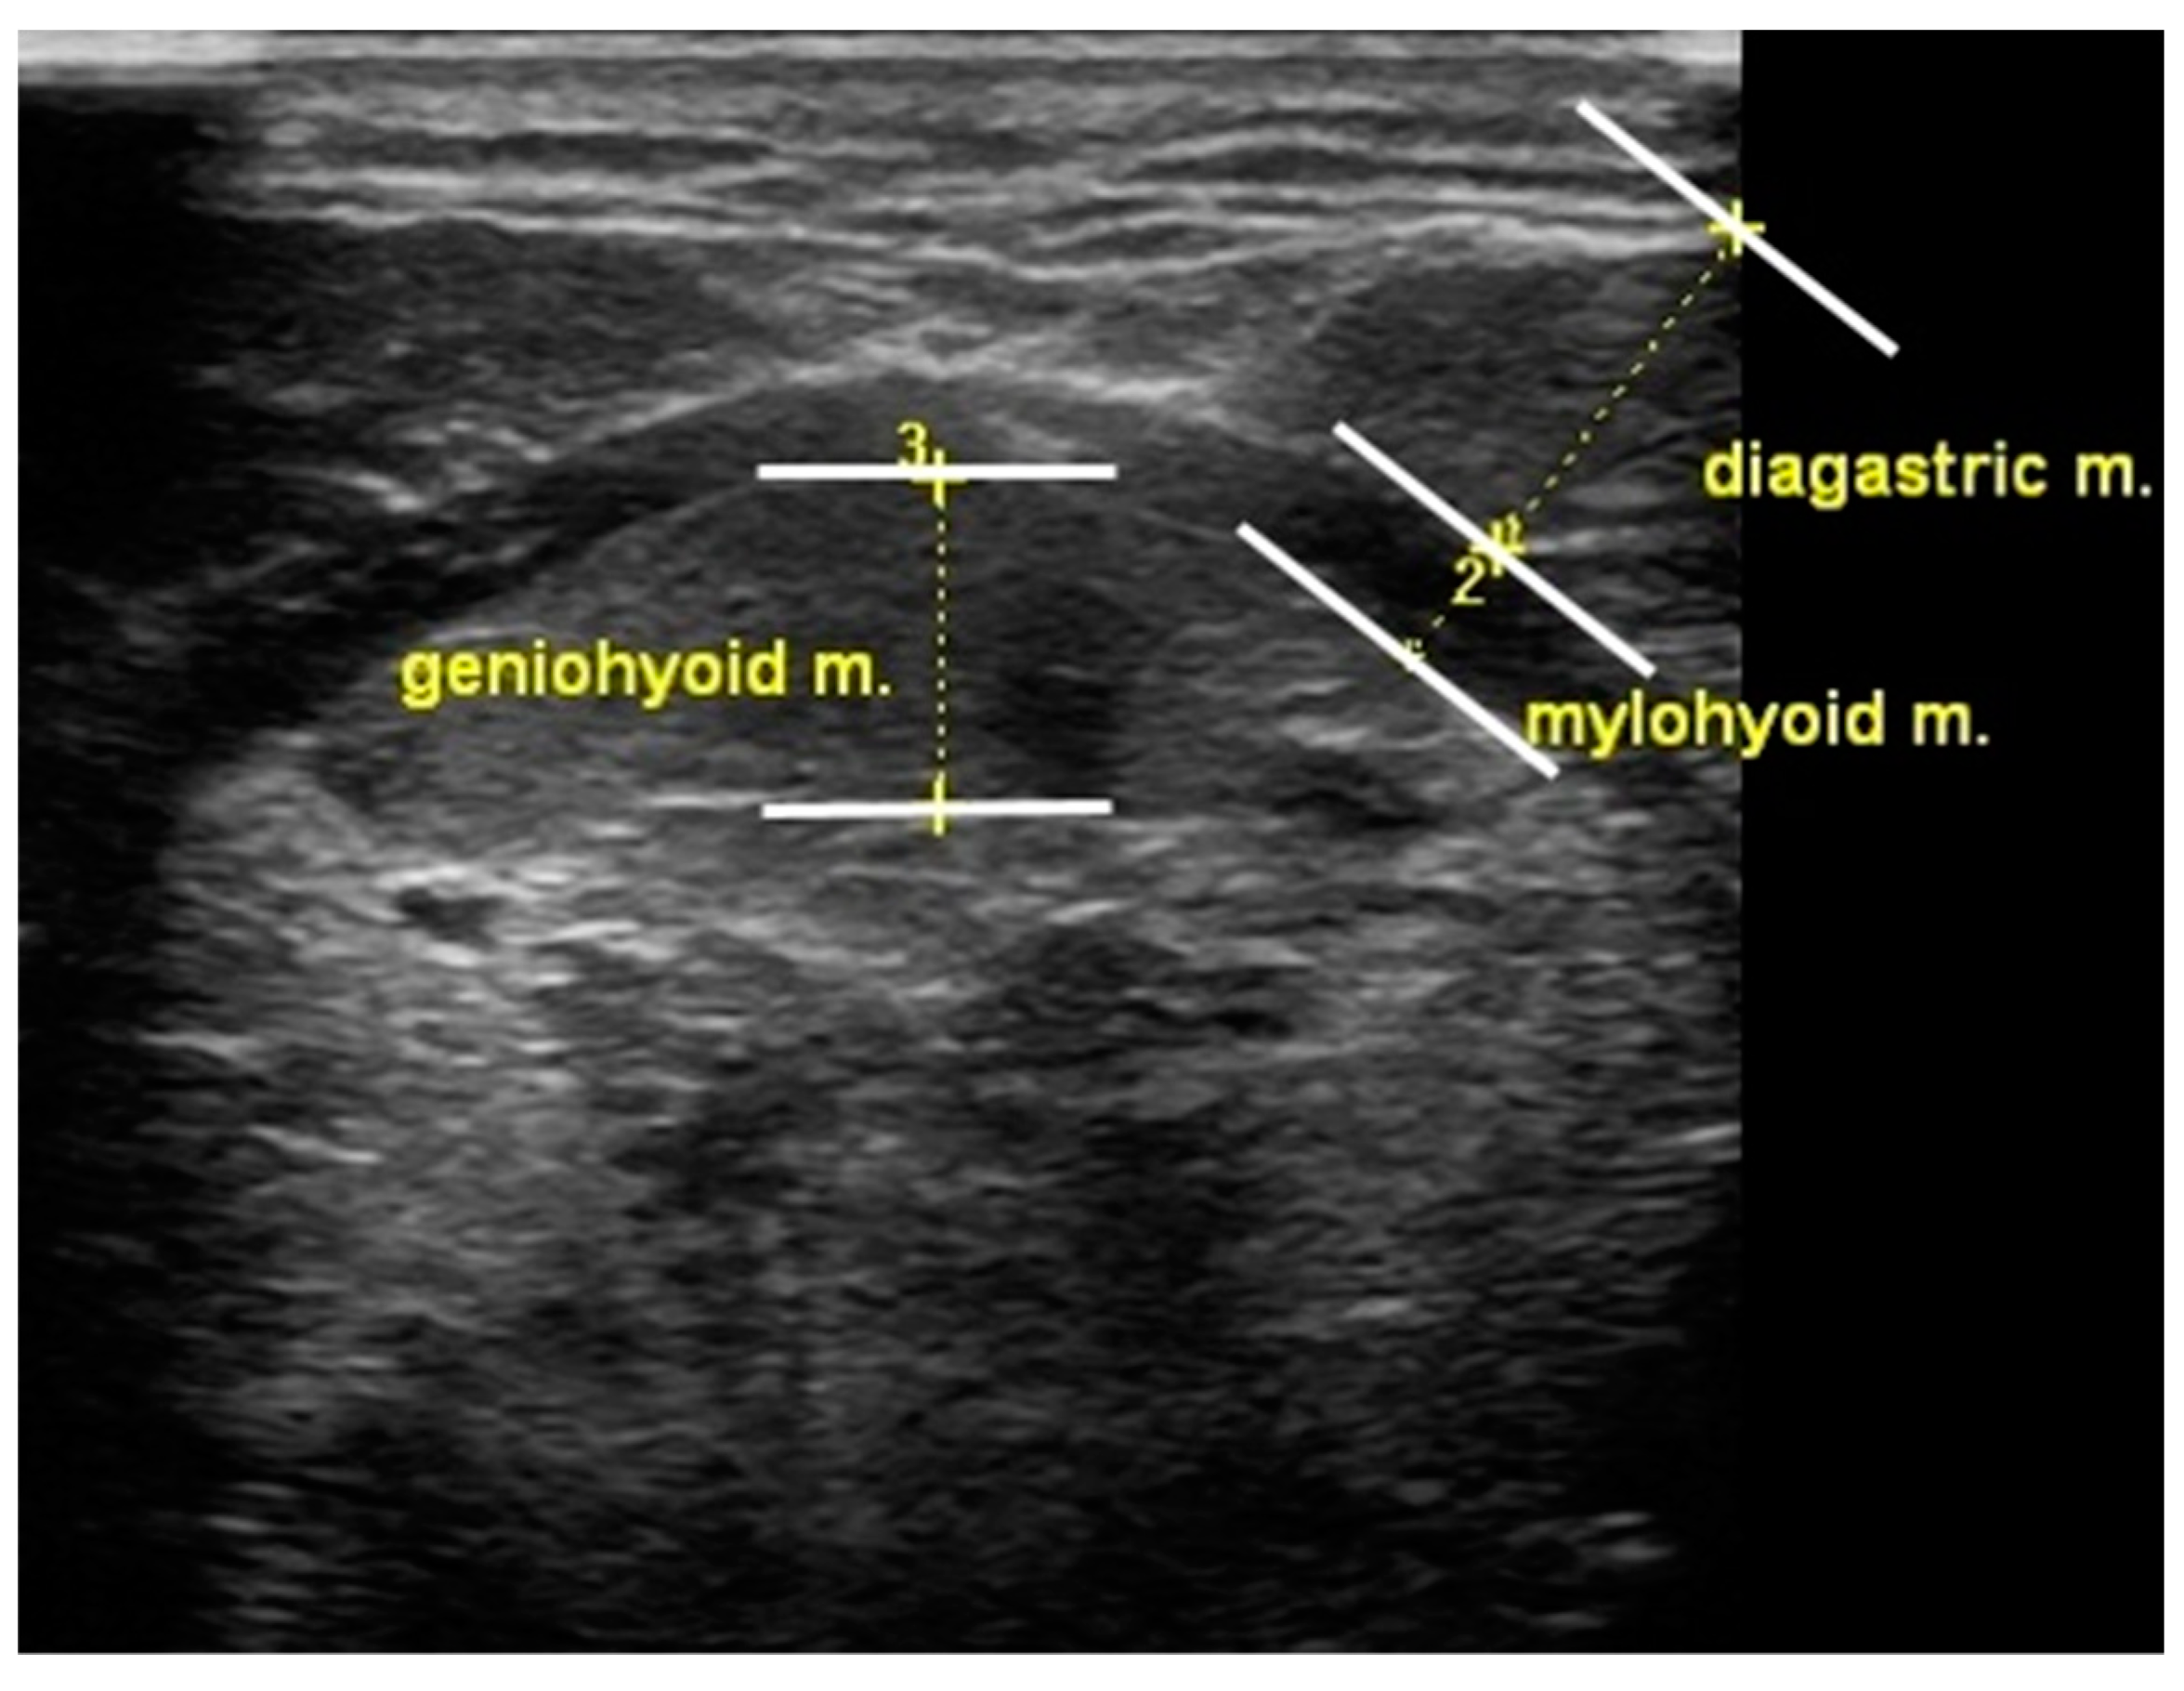

3.3. Suprahyoid Muscle Thickness